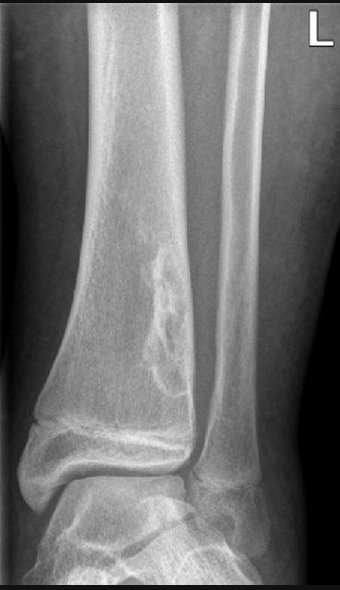

Unicameral/Solitary Bone Cyst

• Usually <30 yo

• Commonly in arm & calcaneous

• Lytic lesion, commonly with fracture

• Fallen fragment sign